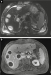

Filmsequenz zu Abbildung 7: Film 3 Kontrastmittelsonographie der Leber im Dualbildmodus (rechts: CEUS; links: normale B-Bild-Sonographie): Die Abszesse zeigen keinen Kontrastmittel- Wash-in oder -Wash-out im Zentrum. |